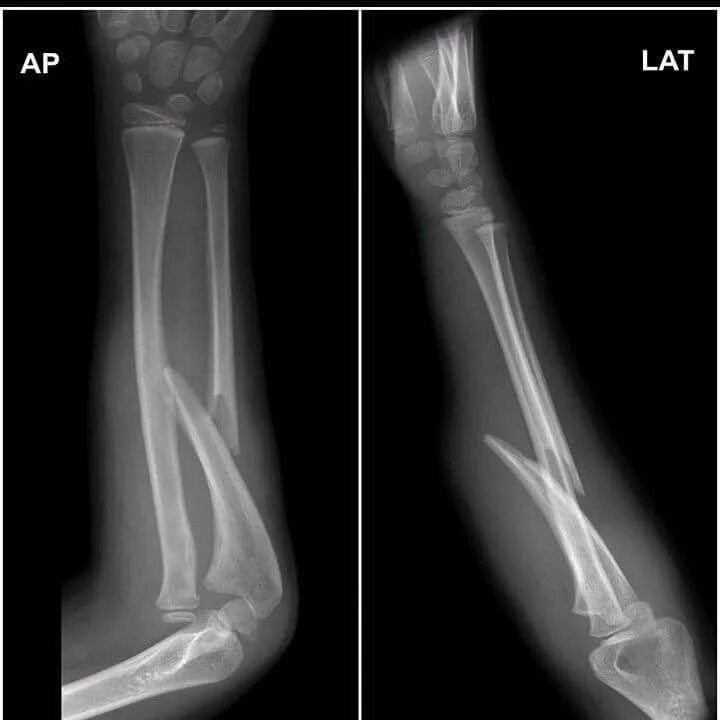

Fracture modeling